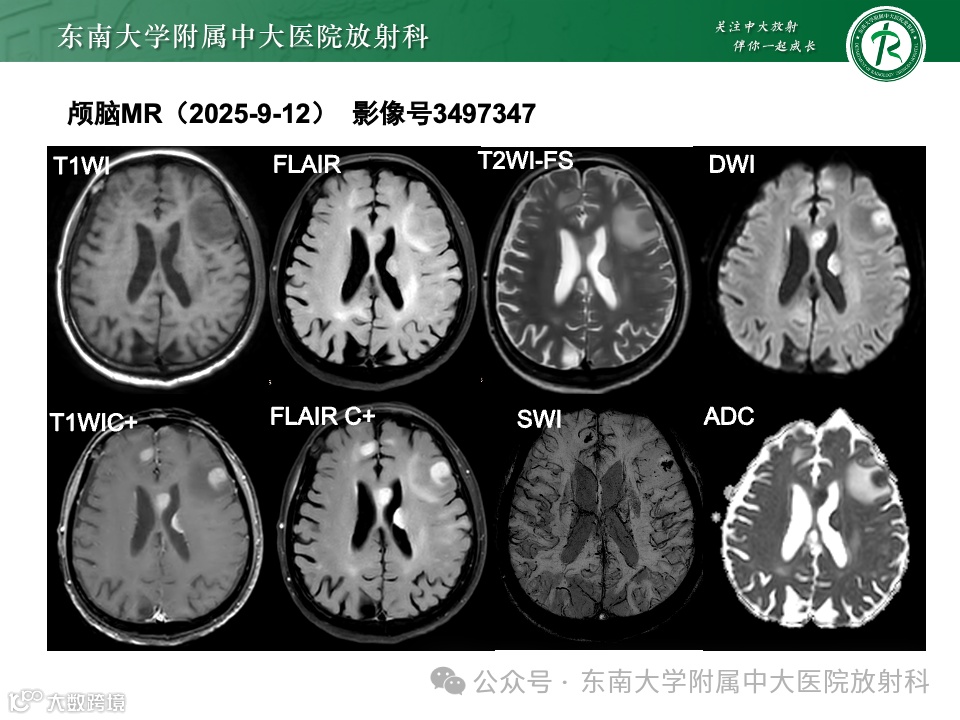

影像号:1217119452 2025-09-08 盆腔MR平扫

影像学表现